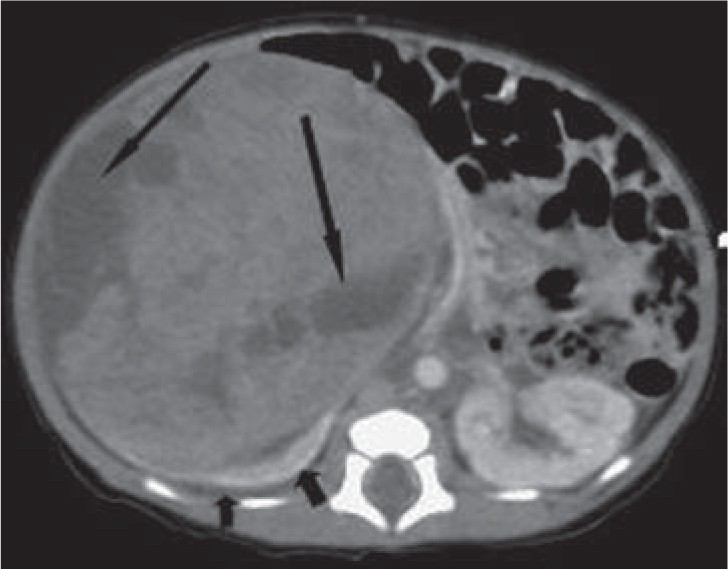

Congenital Renal Masses Obgyn Key